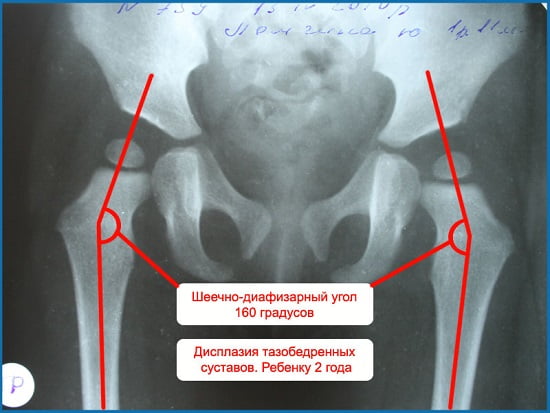

- Рентгенограмма не уступает по достоверности ультразвуковой диагностике, но имеет ряд существенных ограничений. Тазобедренное сочленение у детей младше семи месяцев просматривается плохо в силу низкого уровня окостенения этих тканей. Детям первого года жизни не рекомендовано облучение. Кроме того, уложить подвижного малыша под аппарат с соблюдением норм симметрии проблематично.